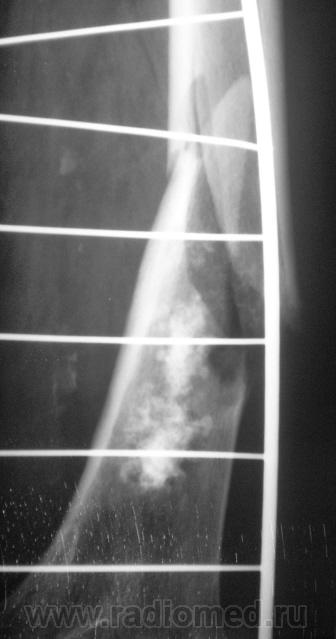

Ну, и, после "репозиции".

н\3 бедра со смещением по длине и ширине. Отломки находятся под углом открытым кпереди прим. в 10-15 град.

После репозиции дистальный отломок смещён латерально на ширину кортикального слоя.

А не создается-ли впечатления, что представленный перелом патологический? Первый снимок произведен через час после травмы.

костных структур в проекции прелома, то действительно это патологический перелом. Честно не сразу обратил внимание.

Что это - не скажу (под рукой нет литературы). Но. 1.Процесс опухолевый - в средней части, по заднему контуру отмечается вздутие кости. 2.Относительно длительно текущий - вздутие достаточно протяженное. 3.Пока еще относительно доброкачественный - кортикальный слой созранен. 4. Многоузловой (мультифокальный) - не менее 3-х узлов/фокусов. В зависимости от возраста/пола/анамнеза вполне может быть метастатическим. 5.Перелом все-таки патологический - линия перелома проходит через верхнюю часть патологического субстрата.

Это может оказаться и безобидным обызвествлением костного мозга после инфаркта, хондромой или хондросаркомой. - Уроки Татьяны Валентиновны. Но вздутия не вижу - его в боковой проекции симулирует третий фрагмент в месте перелома. Ну а метастаз - маловероятен... Опять же - "горим" на сочетанной патологии...

Как по мне, так там наоборот, локальное (хотя и на достаточном протяжении) УТОЛЩЕНИЕ кортикального слоя по задней поверхности, хотя и в сочетании с умеренным вздутием.

Данная рентген-картина может быть характерна и для хондросаркомы.

Вот, и у меня зародилась такая подлая мысль о наличии "хондро", и даже очень вероятно хондросаркомы.

хочу поддержать доктора Анатолия Шумакова: перелом вряд ли патологический, обызвествление костного мозга бедренной кости и вероятно стенок сосудов